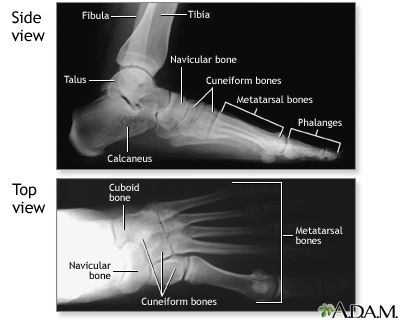

Normal foot x-ray

Normal foot x-ray

Along with questions of your medical history, your doctor may need to take x-rays of your foot to help aid in making a diagnosis to determine the cause of your foot pain. If the foot is broken it will be put into a cast. Toes that are broken are taped.